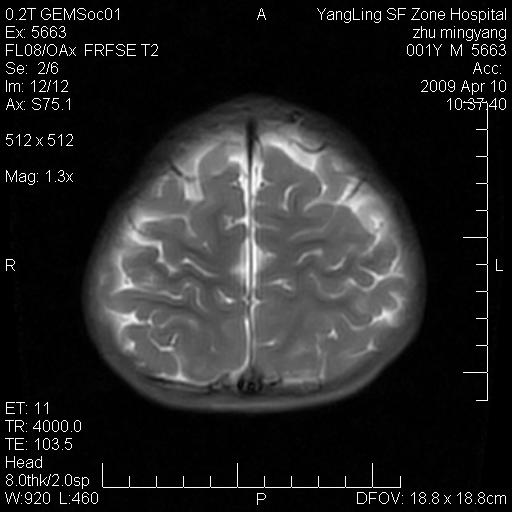

患者:1岁半,两天前外伤收住我院,ct检查小脑占位

考虑星形细胞瘤,建议增强

髓母细胞瘤或血管母细胞瘤,增强后可以鉴别;影像资料见 <。鱼博浪老师的《中枢神经系统ct与mr鉴别诊断》 小脑部肿瘤章节。

髓母细胞瘤或血管母细胞瘤!支持!

支持考虑髓母细胞瘤

考虑----髓母细胞瘤可能性大

考虑髓母细胞瘤或室管膜瘤。

支持髓母细胞瘤。

考虑髓母细胞瘤。

考虑髓母细胞瘤或星形细胞瘤

考虑髓母细胞瘤.

小脑肿瘤.考虑髓母细胞瘤可能.

就病灶部位及临床资料首先考虑髓母.